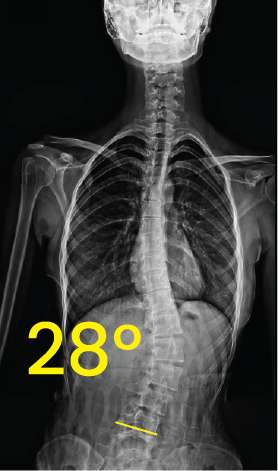

Göğüs ve belde 42 derece eğriliği gösteren omurga röntgeni görüntüsü.Dorsal X-ray image showing spinal curvature with a 28-degree angle measurement indicating scoliosis.